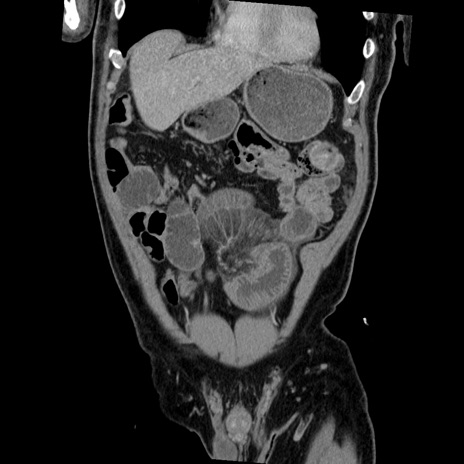

症例22(冠状断像)

【症例】50歳代男性

【主訴】腹痛

【現病歴】AVMからの被殻出血のため回復期リハ病棟入院中。 本日午後3時頃急に下腹部痛が出現した。

【既往歴】AVM、被殻出血、虫垂炎、高血圧

【身体所見】意識晴明、左半身不全麻痺、会話の理解は良好、36.5°C、腹部:膨隆、全体に板状硬、下腹部正中に圧痛点あり、反跳痛-、筋性防御不明、右下腹部にope scar

【データ】WBC 9400、CRP 0.06